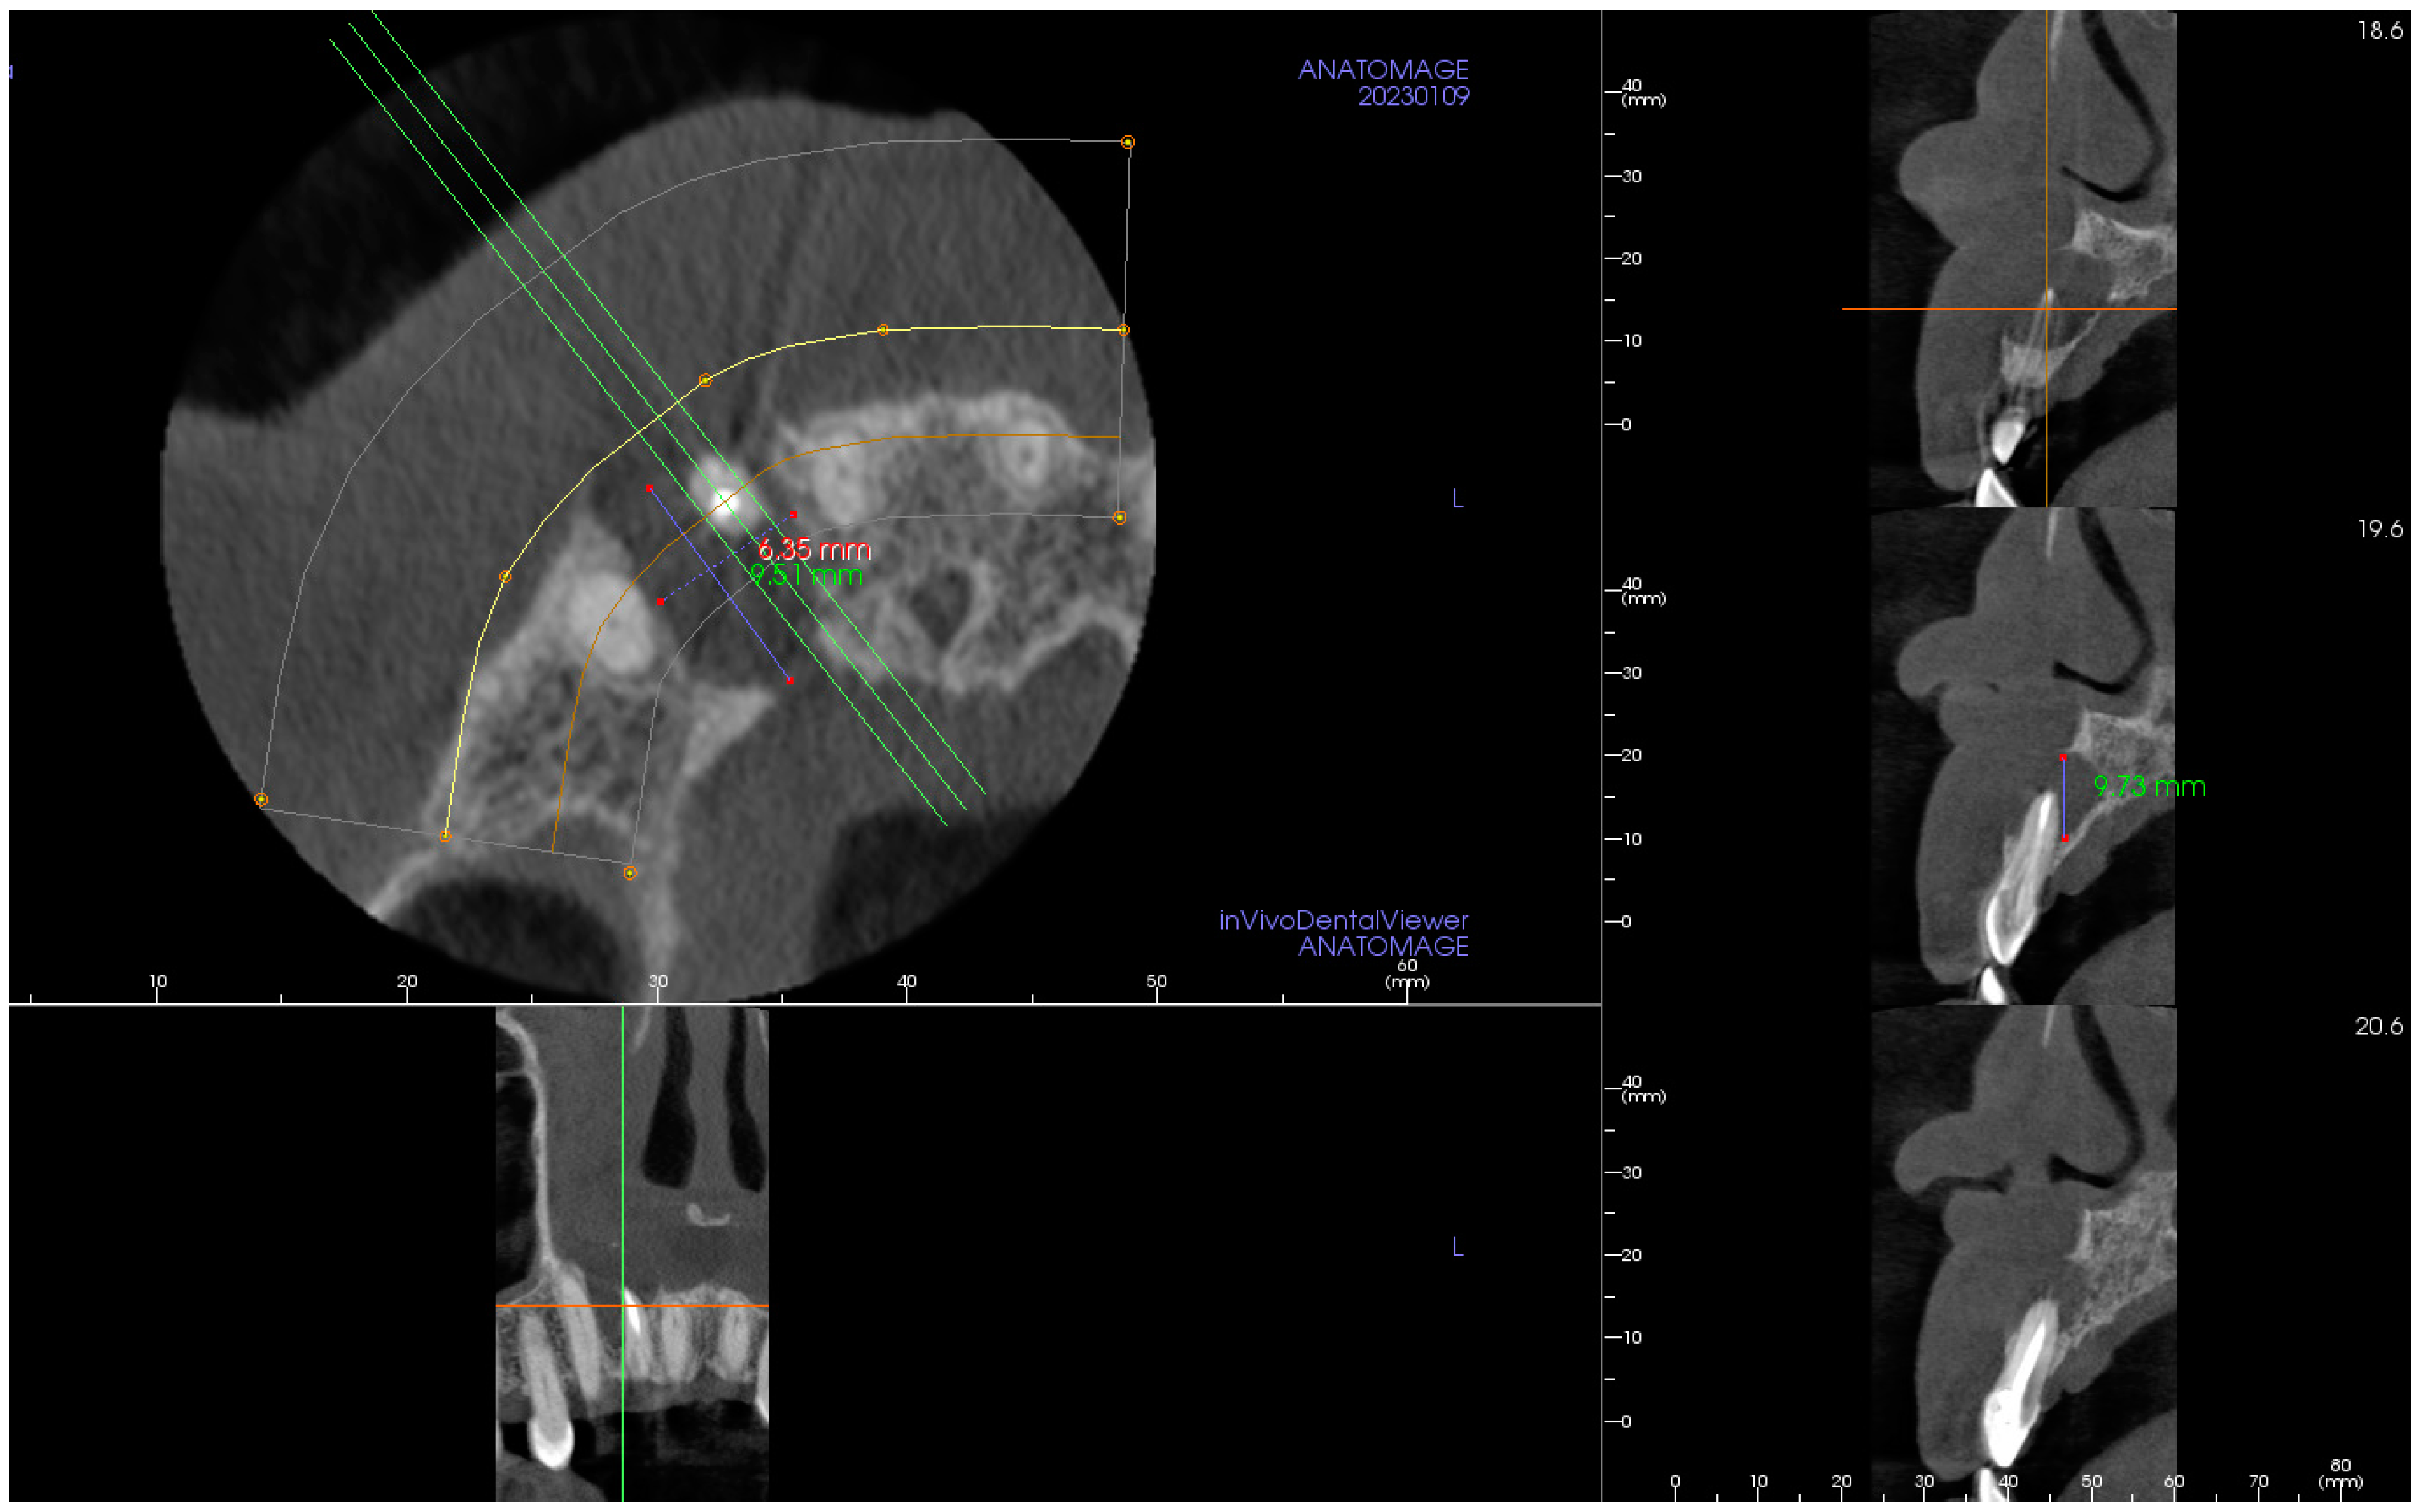

2. The Case